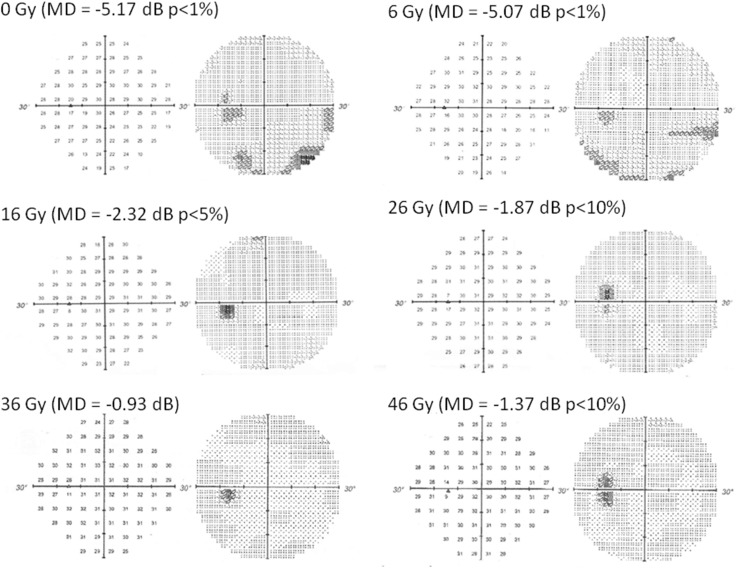

Fig. 1.

A 40-year-old male patient had a low-grade inferior altitudinal defect. Repeated weekly Humphrey automated perimetry showed that the apparent inferior altitudinal visual field defect disappeared rapidly after irradiation of 16 Gy, and the stepwise improvement of mean deviation occurred in visual field during intensity-modulated radiotherapy

We prospectively aimed to detect any early changes in VF occurring during the IMRT course using weekly HAP. An early change in VF was observed during the IMRT. The patient had a low-grade inferior altitudinal defect that has been detected by HAP before treatment. Repeated weekly HAP showed significant stepwise improvements in VF with a change in the mean deviation (MD) of sensitivity depression. At a dose of 46 Gy, HAP showed near-complete disappearance of the VF deficit with an MD of − 1.37 dB (p < 0.1: Fig. 1). Despite this marked improvement in VF, MRI showed little tumor reduction at a dose of 16 Gy (Fig. 2). Although HAP showed complete disappearance of the VF defect with an MD of 0.21 dB, MRI showed continued widening and winding of the ON, as well as only partial regression of the tumor with post-treatment dimensions of 6.5 × 3.5 × 5 mm (volume 0.1 cm3) 2.5 months after IMRT was completed (Fig. 3).